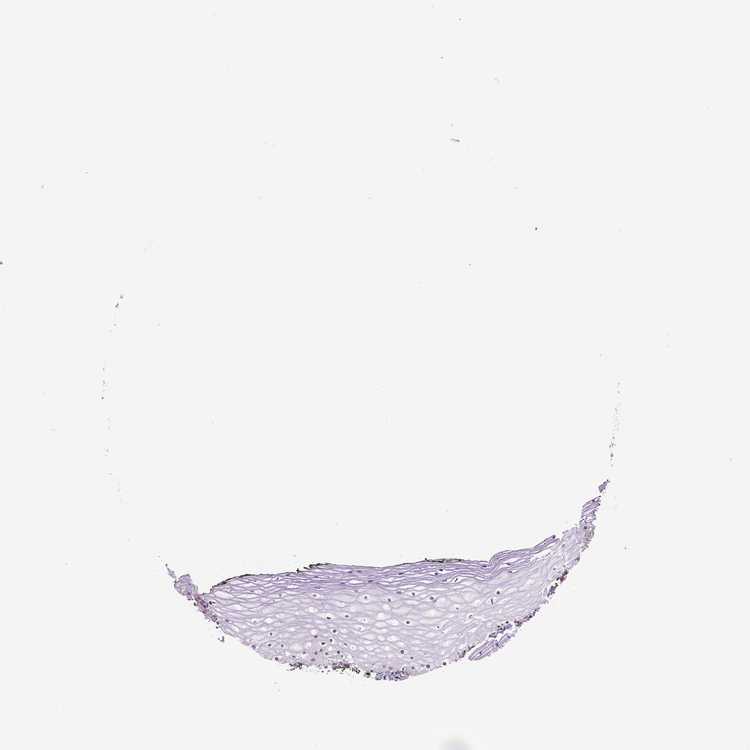

TISSUE PRIMARY DATA VAGINA Show tissue menu

VAGINA - Antibody stainingi

Antibody staining in the annotated cell types in the current human tissue is reported as not detected, low, medium, or high, based on conventional immunohistochemistry profiling in selected tissues. This score is based on the combination of the staining intensity and fraction of stained cells.

Each image is clickable and will lead to virtual microscopy that enables deeper exploration of all samples and also displays staining intensity scores, fraction scores and subcellular localization as well as patient and tissue information for each sample.

Antibody HPA069503Antibody CAB008382

Squamous epithelial cells Not detectedLow